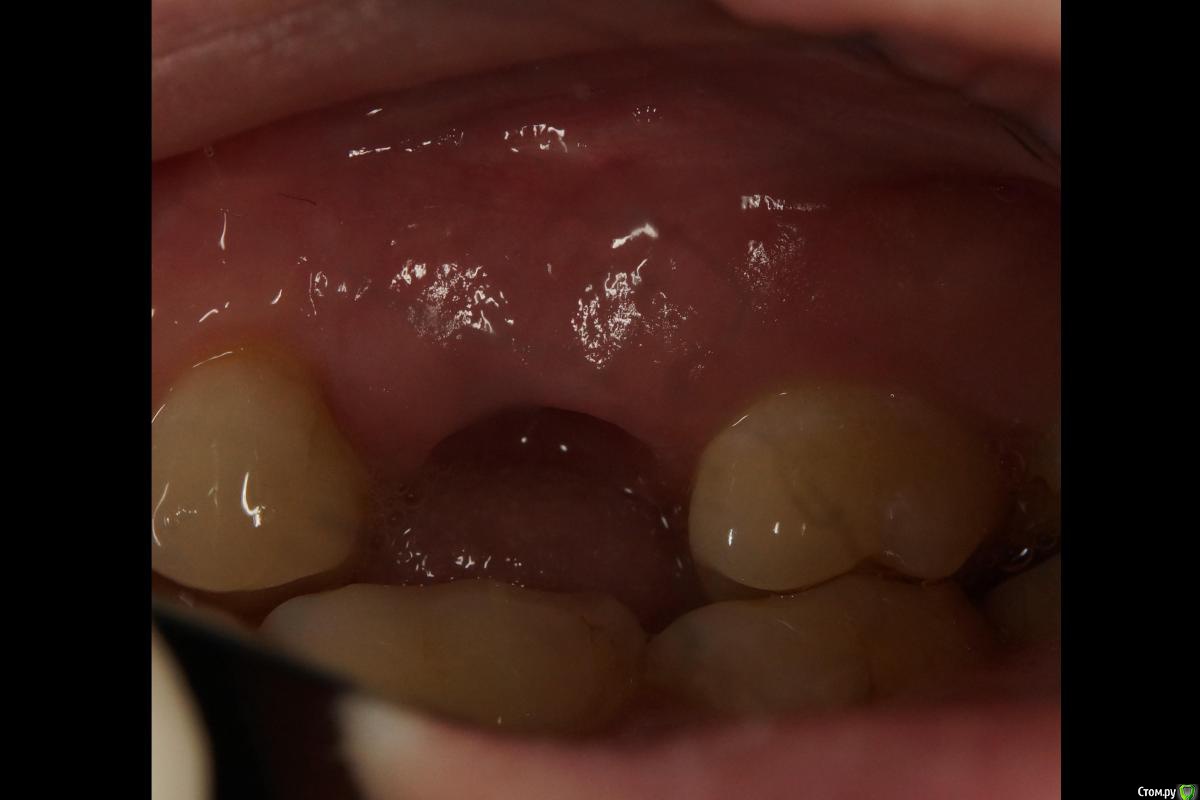

Через четыре месяца проверил торк и пошел шить. Забор отсюда же, сейчас взял бы с бугра, но не жалею - паралельно замастерил рецессию.

Ещё через две недели (на снятии швов) просто облепили напару с ортопедом формик жидким и "индивидуализировали" его.

Месяц с копейками прошел, ждём протезирования. Пациентка затягивает уже три месяца на данный момент, финансы. В этом смысле особо приятно, что аугментация и индивидуализация обошлись в 0 руб. 0 коп.